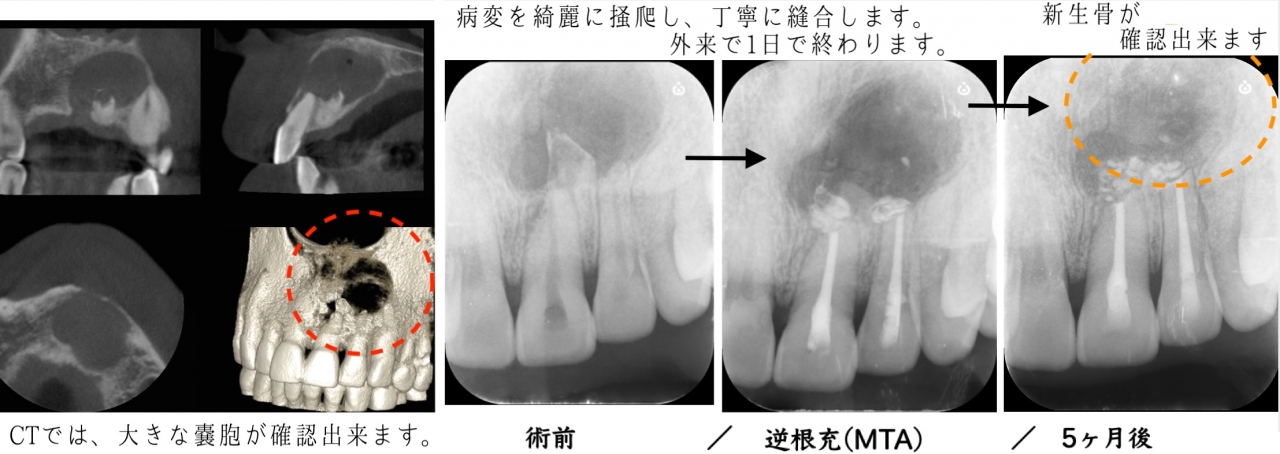

親知らずの抜歯/歯根嚢胞への歯根端切除術なども対応しております。